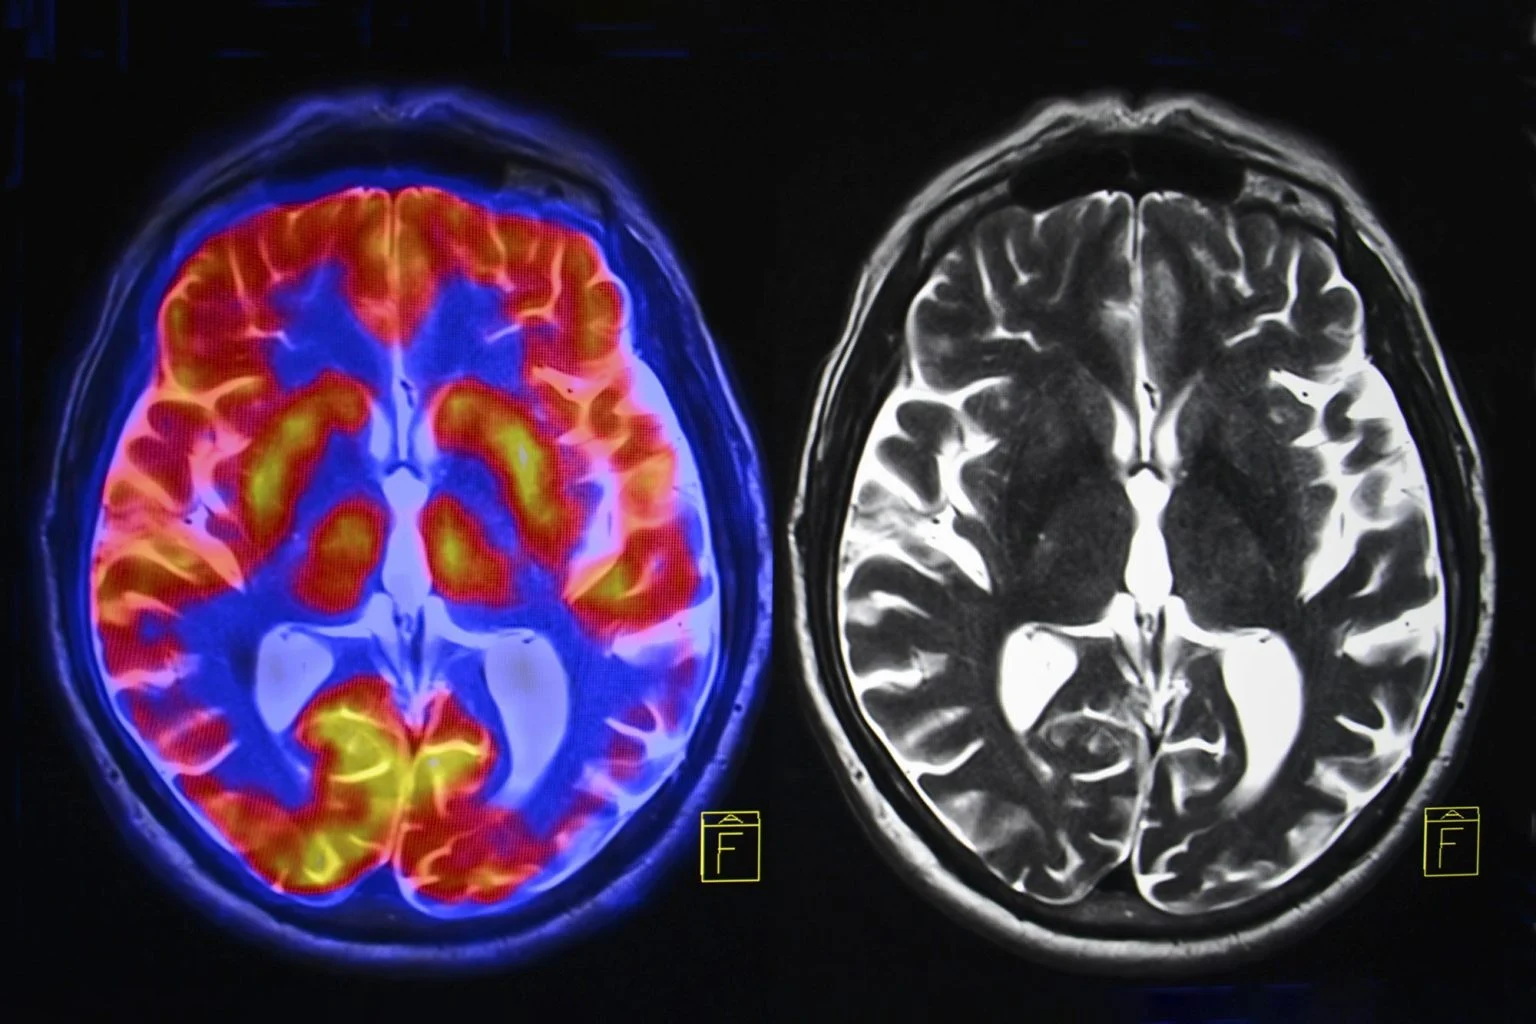

科学家已精准定位帕金森病核心的关键脑网络——初步结果显示,这一发现可能改变该病的治疗方式。图片来源:Shutterstock

这个连接思维与运动的脑网络(SCAN),由华盛顿大学医学院研究人员于2023年首次描述,新研究证实其为帕金森病的神经学基础。一项靶向该网络的实验疗法,使一小部分帕金森病患者的症状改善效果提升超两倍;帕金森病的特征是SCAN与大脑皮层下区域之间的过度连接(图示左侧)。